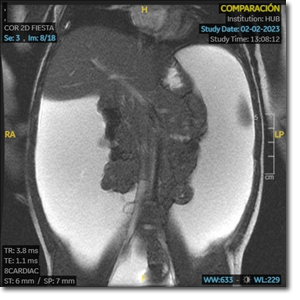

Ni­ña de 2 a­ños con dis­ten­sión ab­do­mi­nal. ¿En qué de­be­mos pen­sar?

Niña de 2 años con distensión abdominal de meses de evolución. No astenia. Buen apetito. No coluria, acolia, ni otra clínica. Peso: 12,3 kg. Talla: 86 cm. Abdomen distendido con cambio de matidez con la postura. Resto sin interés.

Examen analítico con hemograma, perfil hepatorrenal, metabolismo férrico, fólico, B12 y estudio de coagulación normales; marcadores de enfermedad celíaca negativos.